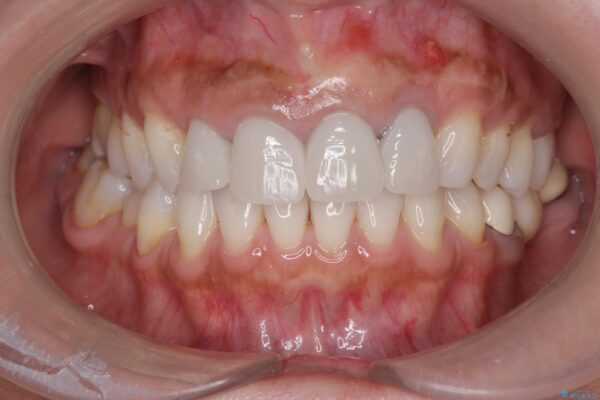

治療前

治療後

歯槽堤保存術を併用したブリッジ治療 治療後画像 歯槽堤保存術を併用したブリッジ治療 治療後画像 歯槽堤保存術を併用したブリッジ治療 治療後画像 歯槽堤保存術を併用したブリッジ治療 治療後画像 歯槽堤保存術を併用したブリッジ治療 治療後画像 歯槽堤保存術を併用したブリッジ治療 治療後画像 歯槽堤保存術を併用したブリッジ治療 治療後画像